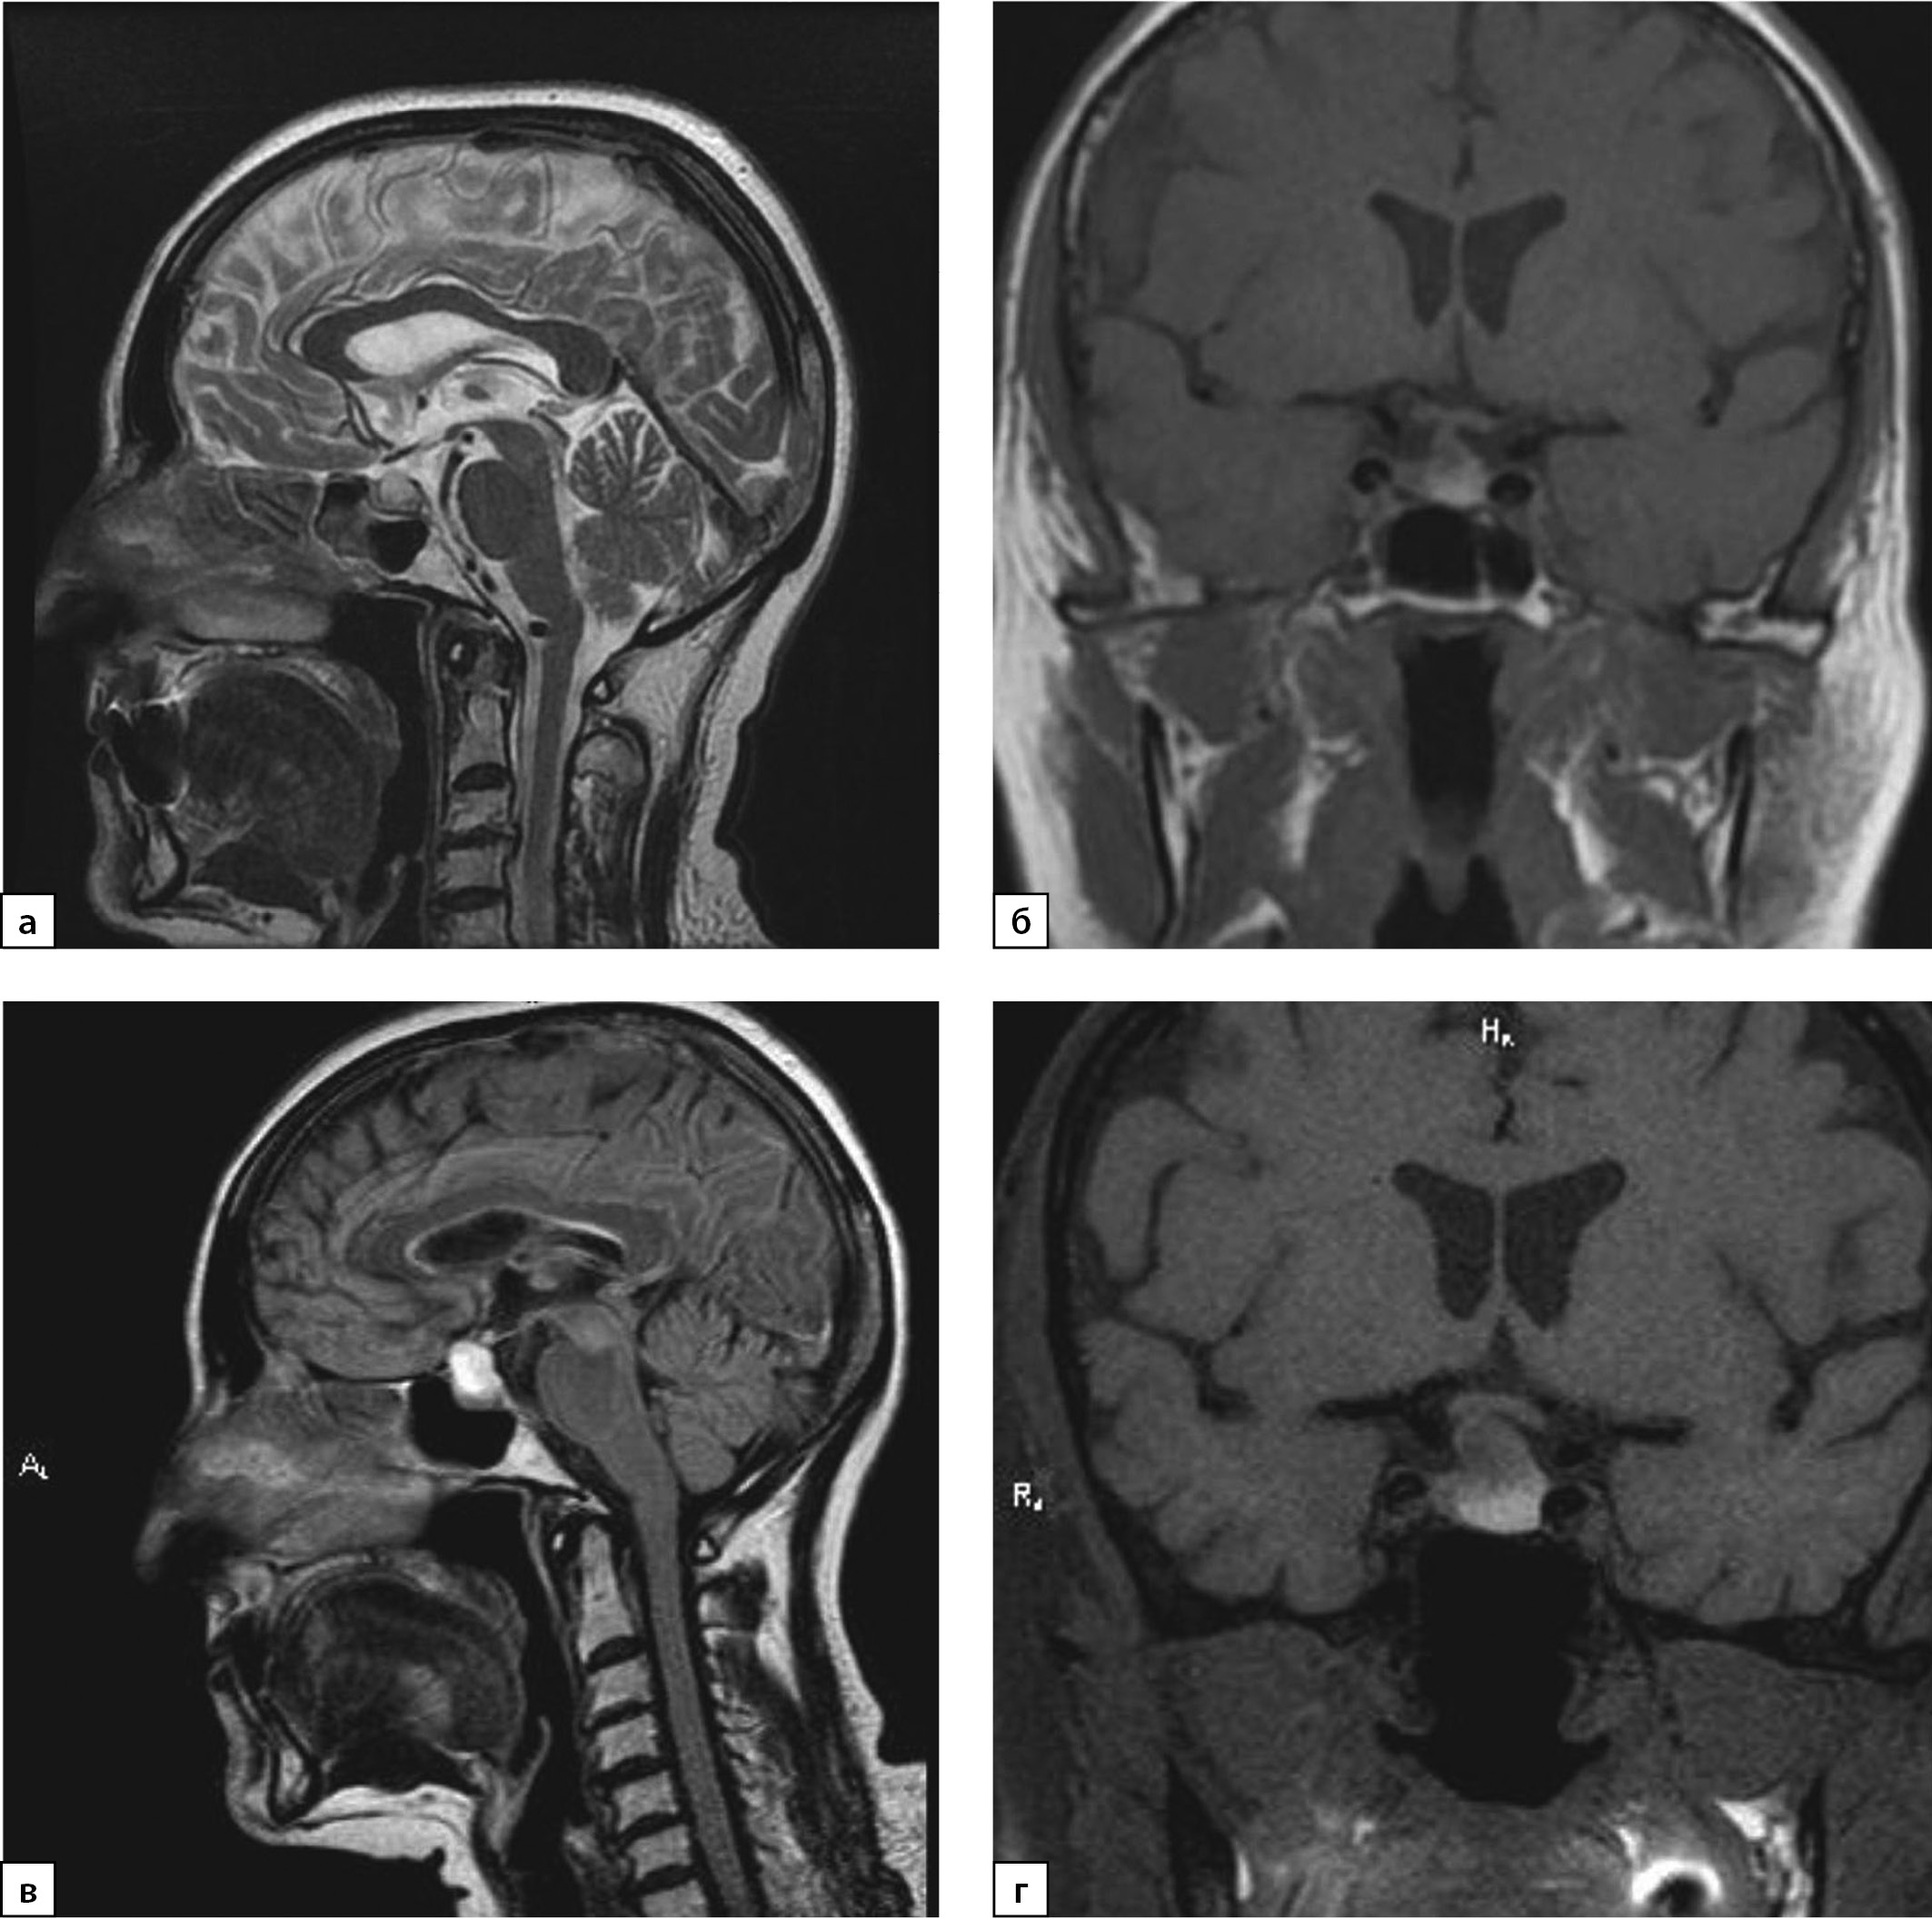

С целью уточнения этиологии центрального гипотиреоза проведена МРТ гипофиза: в аксиальной и коронарной плоскостях в Т2-, Т2d-f- и Т1-режимах, интраселлярно, с распространением супраселлярно определяется объемное образование неправильной округлой формы с четкими, неровными контурами, неоднородной структуры, размерами 1,4×1,1×1,2 см, пониженного МР-сигнала в режиме Т1, повышенного в Т2, Т2df. Отмечаются признаки объемного воздействия: сглажено супраселлярное цистернальное пространство, хиазма оттеснена кверху, воронка гипофиза оттеснена вправо. После введения контрастного вещества отмечается слабое неоднородное накопление последнего небольшой зоной, размером до 4 мм (рис. 1 в, г).

Рисунок 1. МРТ от 2019 г.: а) Т2-ВИ, сагиттальный срез; б) Т1-ВИ, корональный срез. МРТ от 2021 г.: в) Т2 FLAIR-ВИ, сагиттальный срез; г) Т1-ВИ, корональный срез.

Примечание. ВИ — взвешенное изображение.

Figure 1. MRI from 2019: a) T2-WI, sagittal section; b) T1-WI, coronal section. MRI from 2021: c) T2 FLAIR-VI, sagittal section; d) T1-WI, coronal section

В ноябре 2021 г. пациентка по собственному желанию в одной из клиник г. Москвы выполнила МРТ головного мозга. Сохраняется МР-картина эндосупраселлярного объемного образования размерами 18×13×14 мм, в дифференциальный диагноз следует включить макроаденому гипофиза и краниофарингиому. При сравнении с представленными снимками МРТ от 11.11.2019 г. отмечается увеличение размеров образования, от 27.07.2021 г. — динамических изменений нет. Таким образом, ревизия МРТ исследования от 2019 г. свидетельствовала об имевшемся, но не описанном ранее образовании гипофиза меньших размеров (рис. 1а, б).